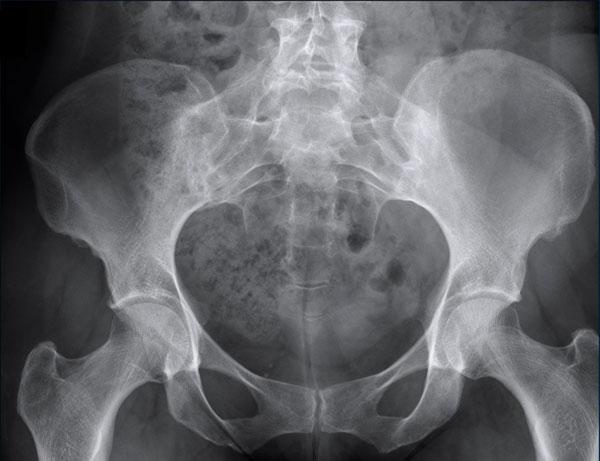

Trong trường hợp này, ban đầu nghi ngờ u xương.

Có một số dấu hiệu có thể gợi ý chẩn đoán u xương tạo xương (osteosarcoma) hoặc u sụn (chondrosarcoma).

Tuy nhiên, trường hợp này đã được xác nhận là gout.

Tiếp tục với hình ảnh DECT…

Với các hình ảnh DECT này, không còn ai nghi ngờ về chẩn đoán nữa.